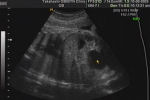

ヒトの誕生

35週目の様子